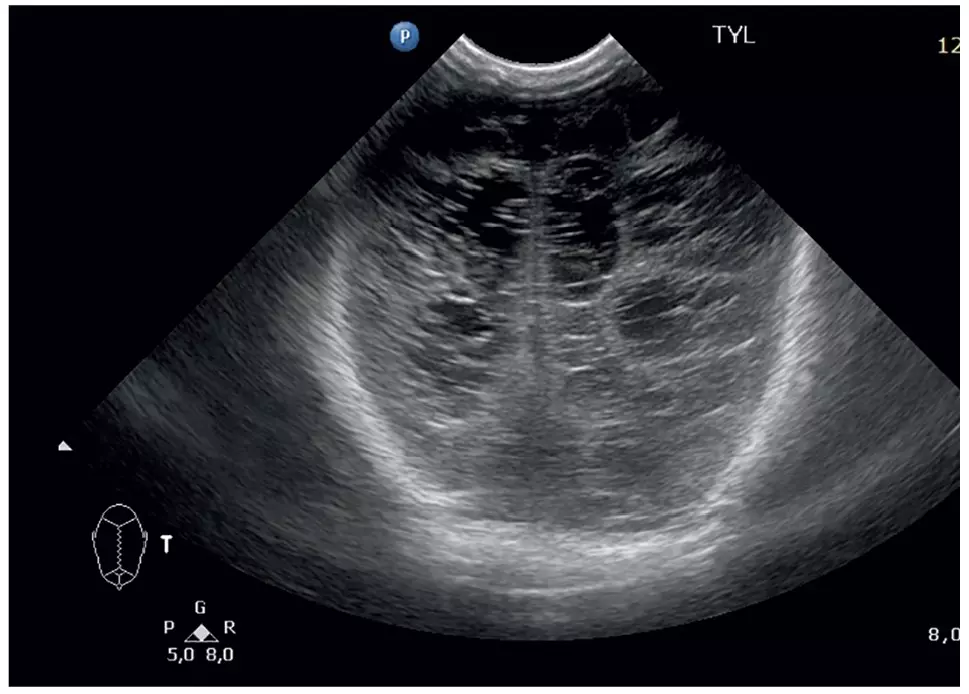

Ryc. 2. Leukomalacja okołokomorowa (PVL)

W wykonanym w 1. d.ż. badaniu USG mózgowia asymetryczne poszerzenie komór bocznych mózgu. Stan po świeżym IVH II st. prawostronnie oraz przebytym wewnątrzmacicznie krwawieniu do komory bocznej lewej. Niewielka jama PVL w okolicy rogu czołowego komory bocznej prawej. Zwiększona echogeniczność okołokomorowa. Prawidłowe przepływy mózgowe. W kontrolowanym w kolejnych dniach hospitalizacji badaniu USG następowała ewolucja krwawień dokomorowych, nie obserwowano nasilenia PVL. W badaniu dna oka obserwowano stopniowy rozwój i wzrost naczyń pierwotnie nieunaczynionej siatkówki. Przesiewowe badanie słuchu wykonane metodą otoemisji akustycznej – prawidłowe. Odruchy noworodkowe odpowiednie do wieku skorygowanego, prawidłowa koordynacja odruchu ssania, połykania i oddychania, obniżone napięcie mięśniowe. Noworodek został wypisany do domu po 45 dniach hospitalizacji (w 38. tygodniu wieku skorygowanego, karmiony piersią, dokarmiany smoczkiem odciągniętym pokarmem matki). Zalecono suplementację żelaza i witamin oraz kontrolę USG głowy, a także konsultacje – neurologiczną, okulistyczną, laryngologiczną (badanie słuchu) oraz rehabilitację.